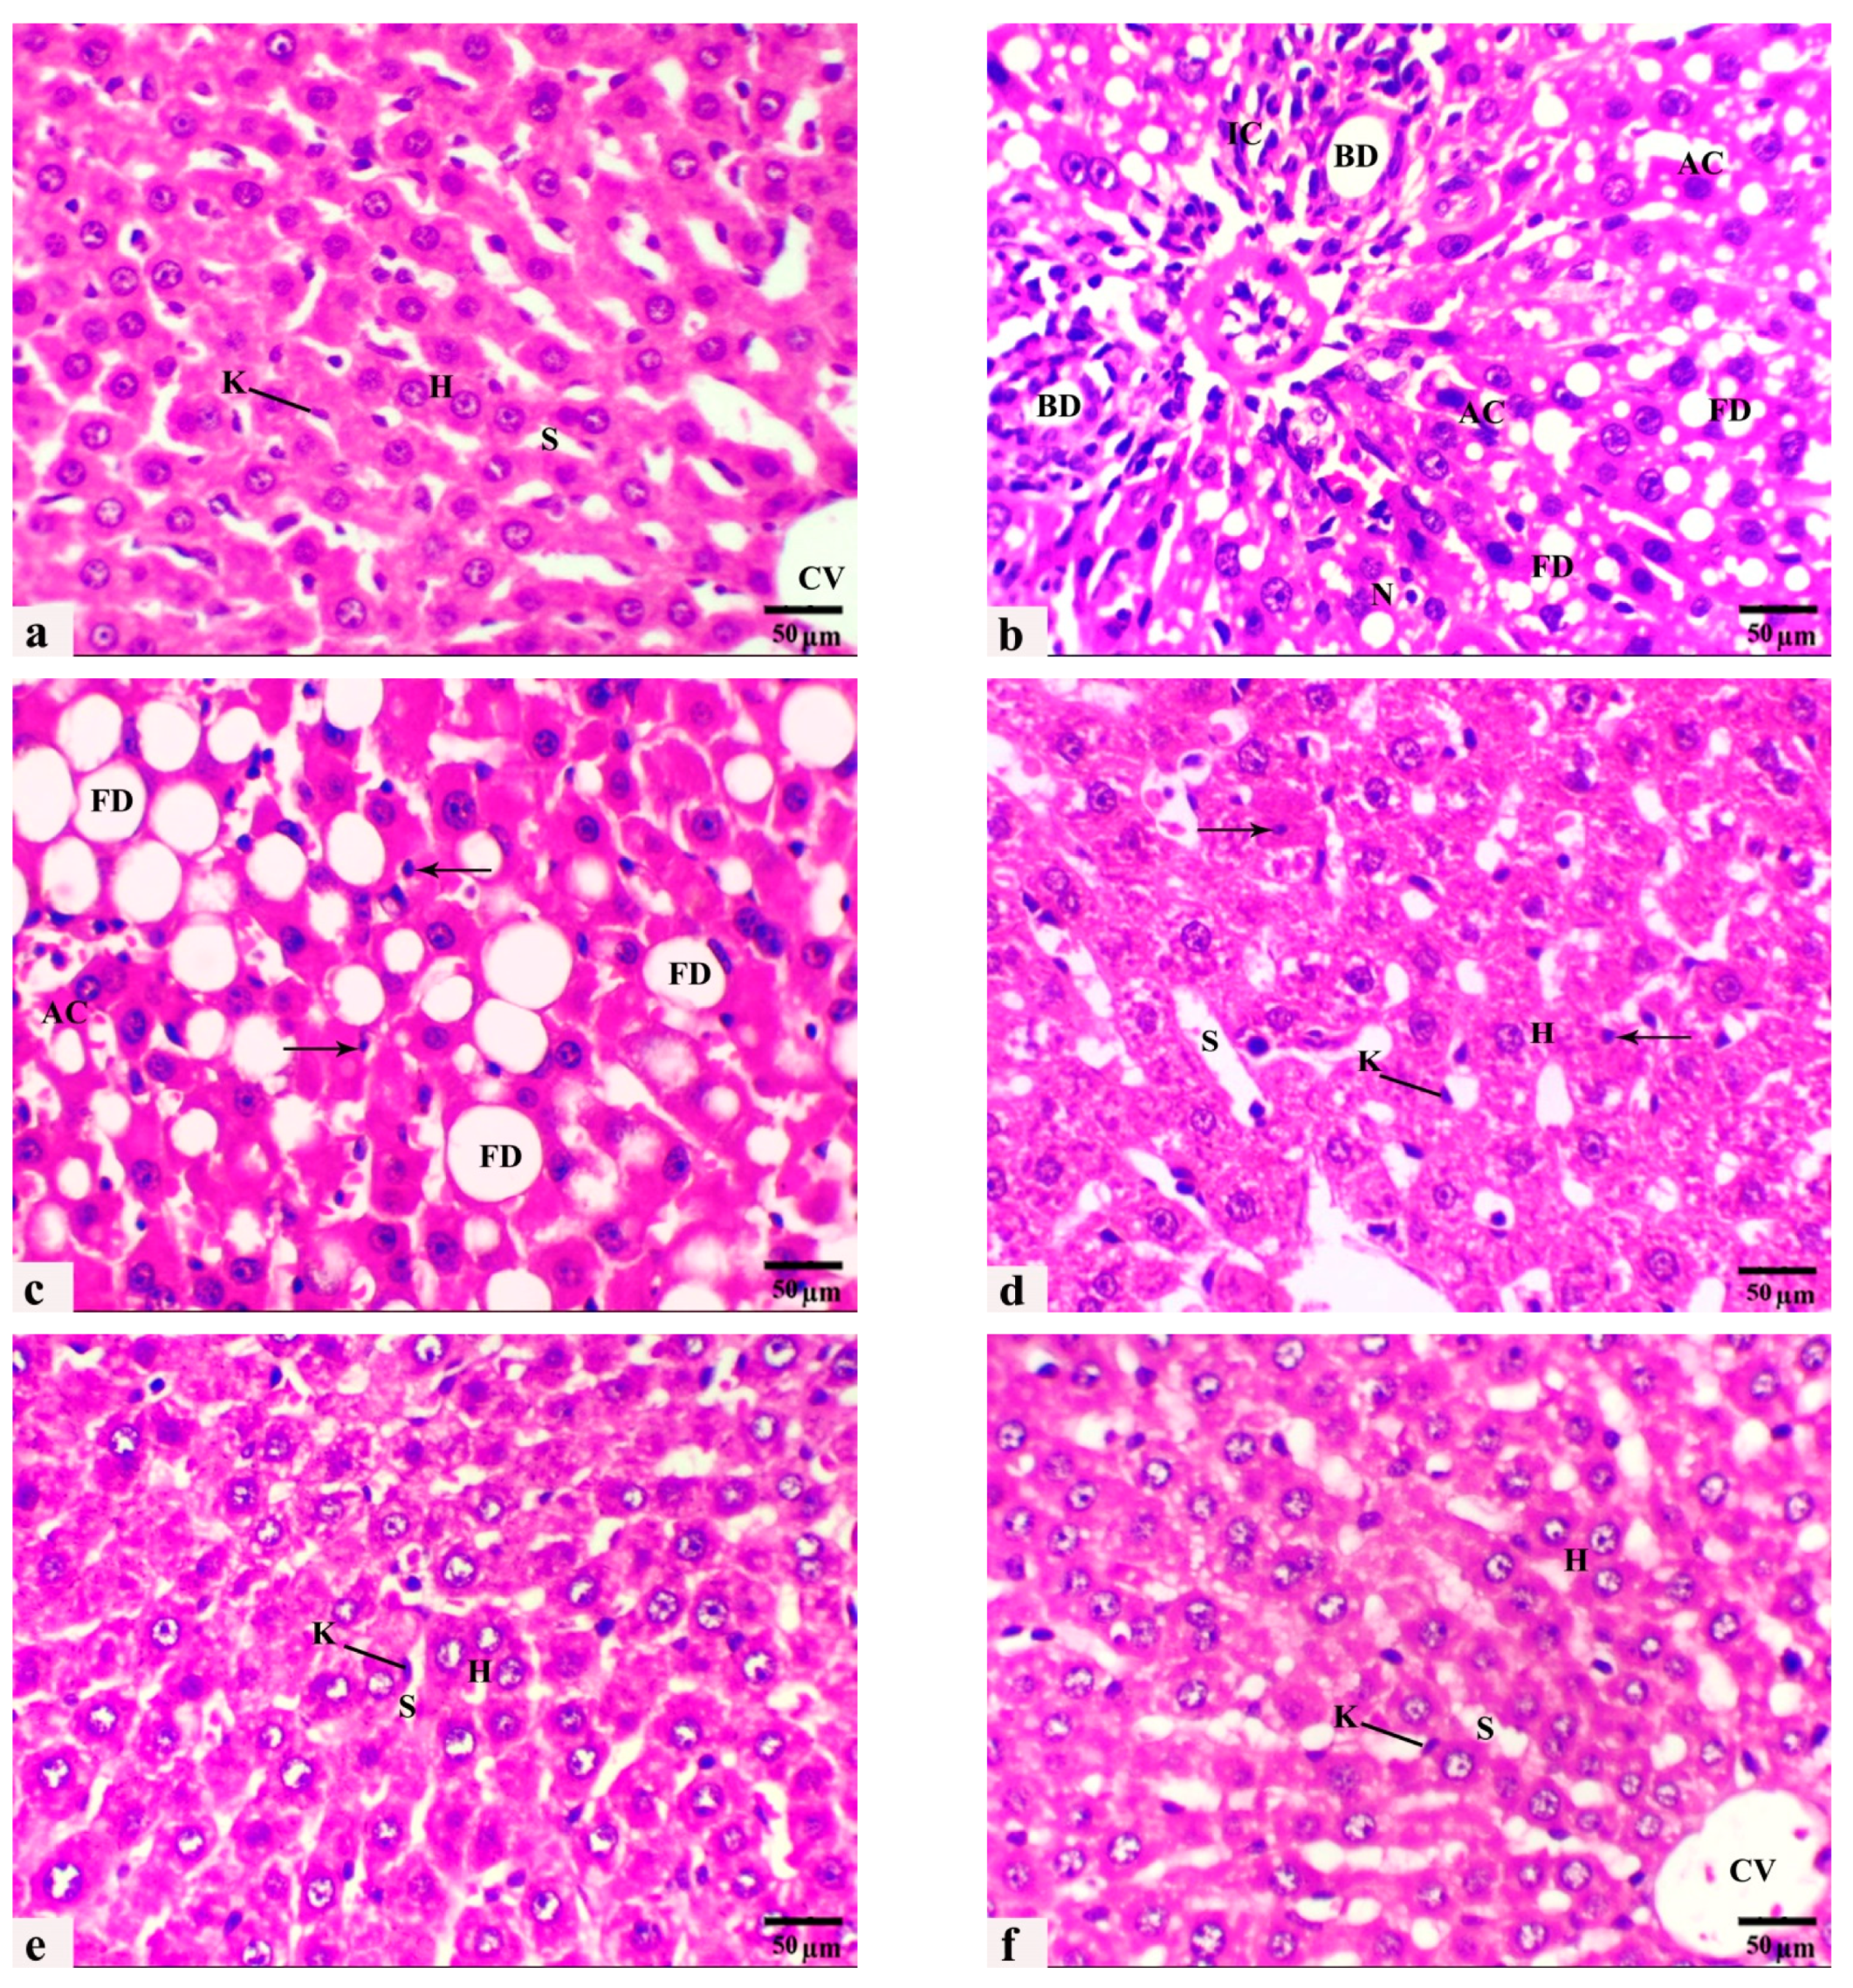

3.4. The Histological Observations